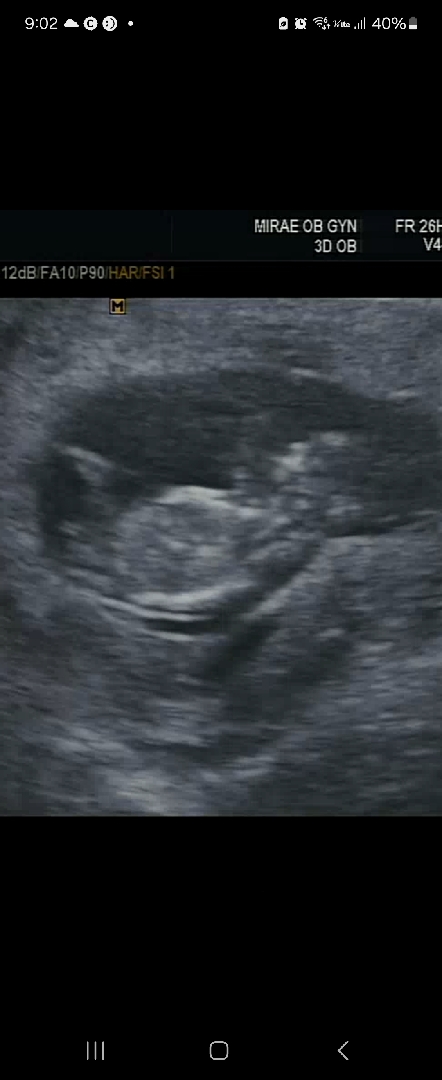

각도법! 너무 궁금해요!

12주 초음파에요. 딸일까요, 아들일까요?